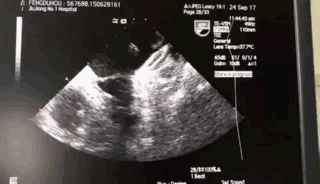

术前超声:

TEE 0:

TEE 45:

TEE 90:

TEE 135:

术中超声:

TEE 135牵拉试验: